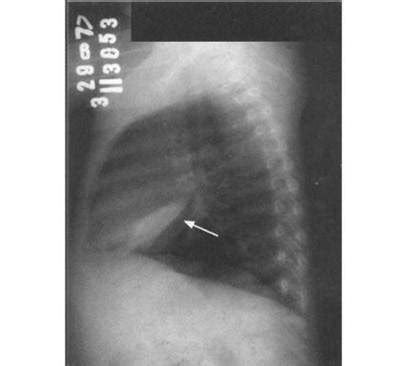

Anatpat-UNICAMP

Anatpat-UNICAMP from anatpat.unicamp.br

INSUFICIÊNCIA RESPIRATÓRIA AGUDA E PNEUMONIA

INSUFICIÊNCIA RESPIRATÓRIA AGUDA E PNEUMONIA from image.slidesharecdn.com